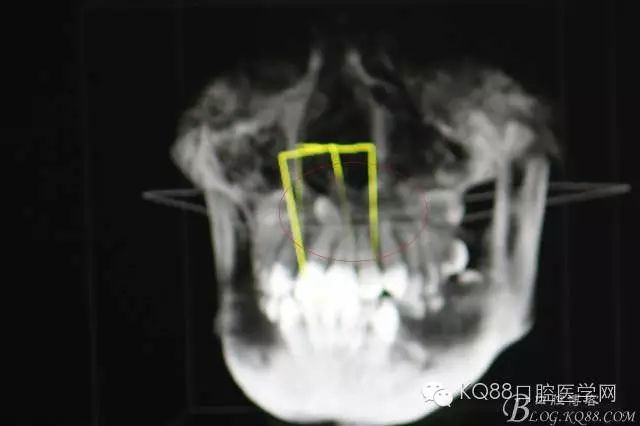

圖3.CBCT三個(gè)方向剖面圖影像:多生牙牙根阻擋11內(nèi)收、牙冠接近鼻底

圖4.cbct的三維重建影像:多生牙牙尖幾乎和鼻底相通